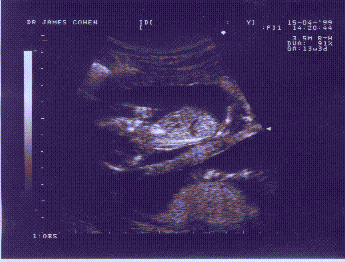

à 3 mois

TIC et TAC ....